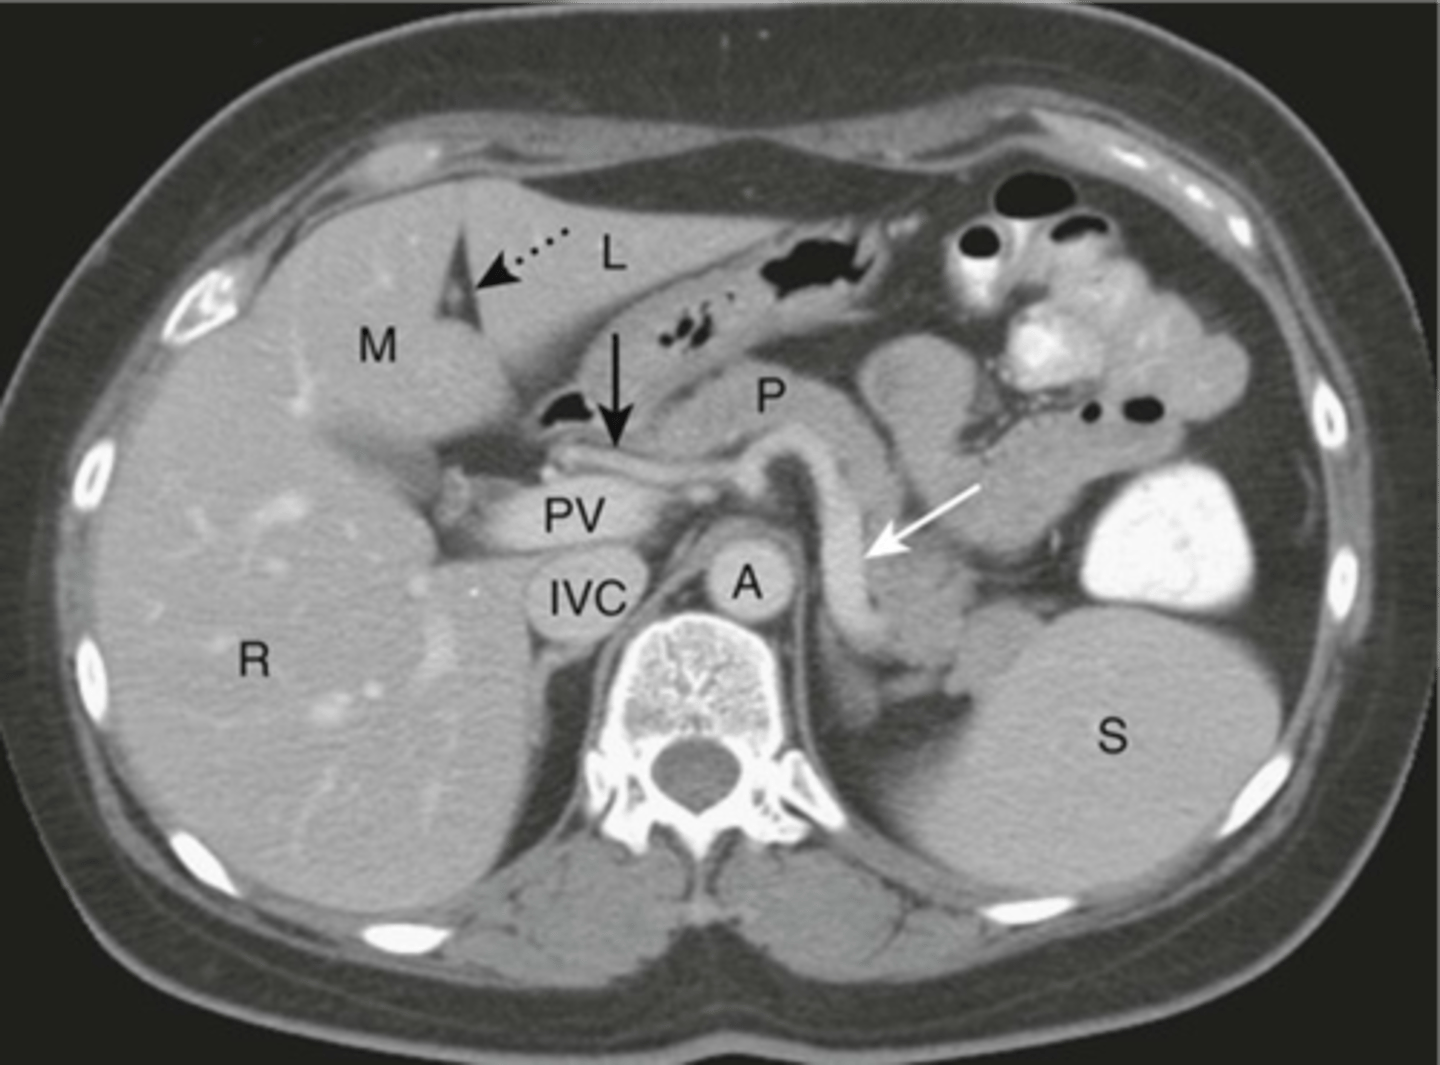

Normal anatomy in axial CT

Normal pancreas CT

Normal CT